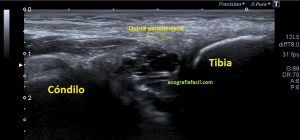

236. Quiste parameniscal.

El paciente es un hombre de 44 años con dolor de rodilla en la cara externa, ha sufrido varias cirugías por meniscopatías en el lado externo de la rodilla mientras realizaba una práctica deportiva, pero de este evento quirúrgico hace ya años. Acude al médico por dolor en la región previamente señalada, su médico le remite para valoración.

Lo primero de todo es saber cómo debemos ver un menisco en la ecografía, para ello debemos buscar la cara lateral, interna o externa que deseemos estudiar, con sonda lineal de alta frecuencia, corte longitudinal o eje largo respecto de la rodilla a estudio, es decir, como si hiciésemos un corte coronal de la misma.

Que debemos encontrar, bien, algo parecido a esto:

Esta es la normalidad, es una imagen preciosa cedida por Javier Álvarez @fisioequilibra, TSID, Fisioterapeuta, Profesor de la Universidad Francisco de Vitoria de Madrid, colaborador del Blog y amigo de los que se cuentan con los dedos de la mano…

Es lo primero que debes buscar, es lo más importante. En la imagen  1 puedes ver un menisco normal y sano, señalado por la flecha hueca amarilla. Semiológicamente es una estructura cónica hiperecogénica, homogénea en la cara externa de la rodilla entre la tibia y el cóndilo femoral, profundo al ligamento colateral, es la parte visible del menisco por ecografía y es tu objetivo en cada exploración de esta zona.

En el caso de hoy, el paciente presentaba una imagen de la zona descrita en la imagen 1 y que ves la imagen siguiente que difiere significativamente de la normalidad.

2

En esta imagen vemos la misma región que viste en la imagen 1, donde claramente ves alterada la semiología de la ecoarquitectura de menisco, heterogéneo, hundido, y en la superficie del mismo, imágenes hipecogénicas muy finas que pueden indicar afectación del mismo. Un poco más superficial e indicado con la flecha roja observas una estructura anecoica, correspondiente a líquido que luego verás en detalle en fotos posteriores.

La afectación del menisco es variable, por supuesto, verás muchos que difieran de la normalidad. En la imagen 2 has visto un menisco afectado, en la imagen 3 vas a ver otro, mira:

3

En la imagen 3 puedes ver un menisco que en su parte central tiene una línea hipoecogénica, bastante sutil, fíjate bien, irregular que lo divide en 2 partes. Pero ¿qué pasa cuando un menisco está dañado? Cuando un menisco por sobreuso, sobrepeso o la razón que sea pueden mostrar cambios en la ecoestructura, ya sea por que se han fisurado, como el de la imagen 2, incluso pueden llegar a romperse. Es fisura o rotura puede ser la vía de escape del líquido intraarticular de la rodilla hacia la parte extraarticular y si eso se produce, podemos encontrarnos con esto:

4

El líquido ya se ha salido y ha formado una bolsa situada superficial al menisco, profundo al ligamento colateral y que está señalado con flecha amarilla. Marcadamente anecoico puedes verlo en tamaños variables en función el alcance del líquido que haya salido y en función de las variantes propias de cada paciente.

La presentación de éste era así:

5

Semiológicamente ves una ecoestructura anecoica con septos hiperecogénicos paralelos en alguna porción del quiste que no muestra vascularización. Este estaba en torno a los 2,5 cms, en el momento de la exploración.